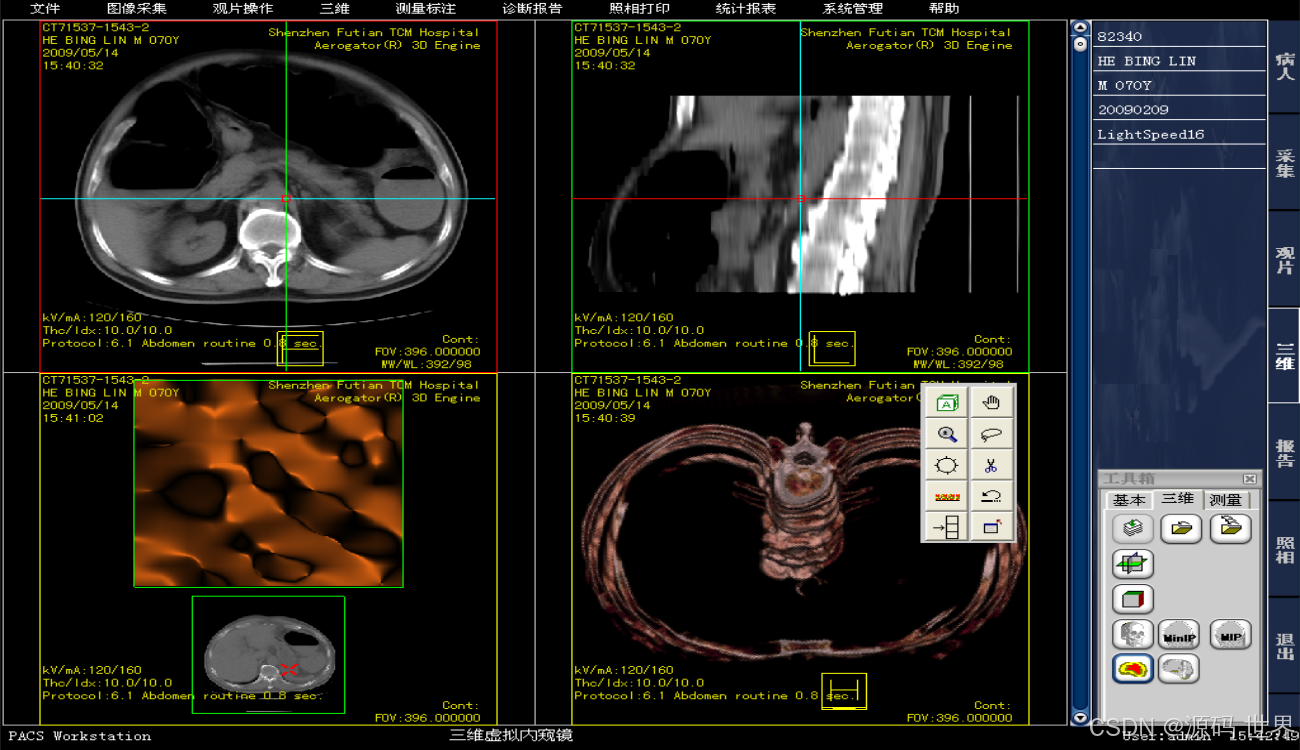

图像处理:三维功能、关键图像和GSPS的标记、DICOM SR信息的支持、各种类型图像专业的图像处理功能。

● PACS 工作站

医学影像工作站主要用于从PACS服务器快速调阅影像,对调阅的影像进行后处理,影像标注,测量,胶片打印等功能。医学影像工作站和诊断报告工作站可以共同组成双屏工作站,用于影像科室书写诊断报告,替代原有的胶片+灯箱+ 纸笔+ 手写的工作方式。